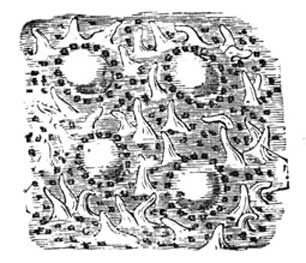

Fig. 1.—A bit of the inner coat of the small intestine.

Fine threads of blood vessels (capillaries) take it up from the stomach and intestines. Also along the intestines there are little projections (villi), through which the food passes into a blood stream leading to the liver, where the blood is then purified. These projections also contain lacteals or little vessels containing blood without its red corpuscles. A duct carries this colourless blood mixed with absorbed food to the left side of the neck, where it empties into the blood stream. These lacteals have a special affinity for the fat of the food. Most of the rest of the food, including the proteid and the carbohydrate or starchy portion now in the form of sugar, passes into the capillaries, and then is led to the liver.

The liver will not let through more sugar than is required, storing it up for future use. It also acts as a careful guardian, by arresting many poisons which would otherwise pass into the general circulation. The liver requires for the proper performance of its functions plenty of pure blood, hence the necessity for fresh air and exercise, that the lungs may work well. The liver is easily influenced by alcoholic beverages, and by getting too hard work to do through eating rich foods. A consideration of this delicate and intricate process, whereby the digested food is absorbed, will show that badly-digested food can not hope to be well assimilated, consequently attention should be paid to the quantity and quality of the food we eat (see Digestion; Diet).

Fig. 2.—Two villi containing lacteals. The white canals are lacteals, the darker lines indicate blood vessels (capillaries). Magnified 100 diameters.

(From "Quain's Anatomy.")

Whatever thus makes living substance is nourishment; whatever fails to do so is not. If food be taken, and even digested, without being thus assimilated, it becomes an injury to a patient instead of a help. In cases of fever, inflammatory disease, or wasting sores, much rich food feeds the fire. It is like laying rafters on the roof of a burning house for purposes of repair. In such a case small quantities of milk, or milk and hot water (see Digestion), represent the total food which can be effectively used in the body. We write on this subject that in treatment our friends may watch not to injure by making the blood too rich in elements which the system cannot usefully assimilate. Such foods as oatmeal jelly and wheaten porridge will often furnish more real nourishment than pounds of bread, beef, and potatoes. A little careful thought will guide to correct treatment in this matter. An easily assimilated diet is found in Saltcoats biscuits and hot water; many inveterate stomach troubles have yielded to this, when taken as sole diet for some weeks (see Biscuits and Water).